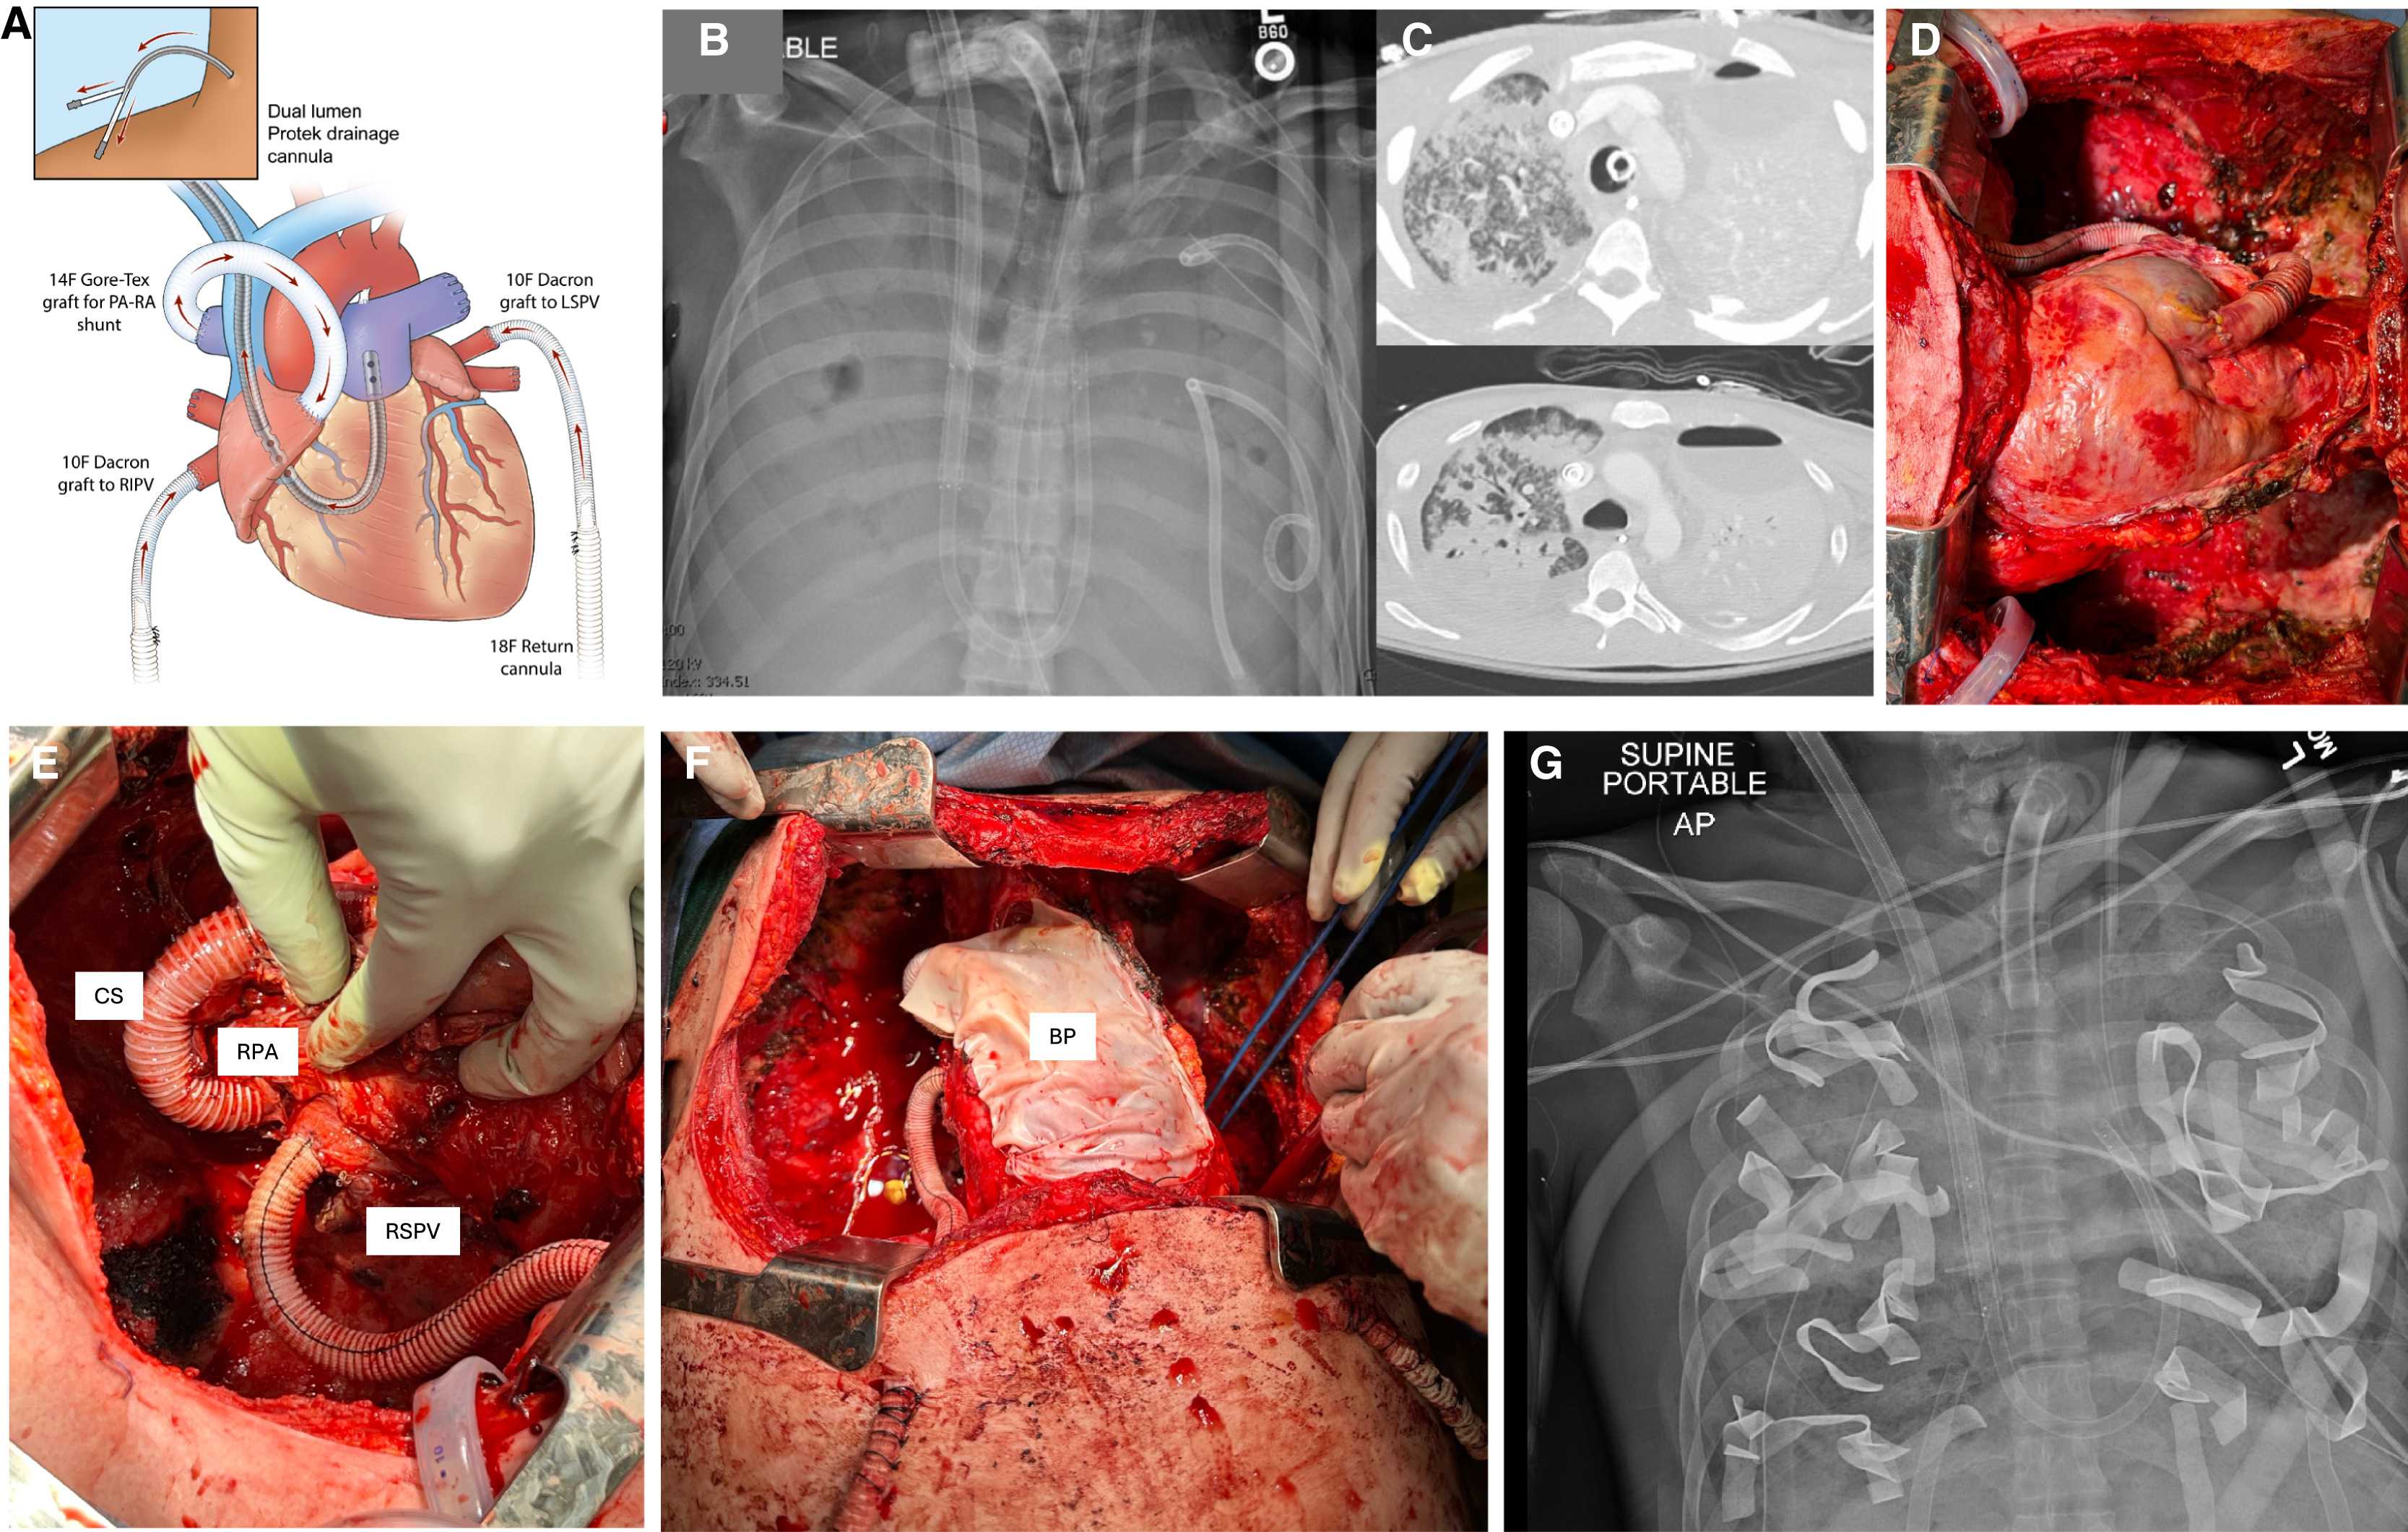

Торакальный хирург Анкит Бхарат (Ankit Bharat) с коллегами по Северо-Западному университету в Чикаго разработали экстракорпоральную систему, которая функционирует как полностью искусственное легкое, способное осуществлять газообмен и выполнять функции буфера кровообращения после двустороннего удаления легких. Она включает адаптивный к потоку крови шунт между правой легочной артерией и правым предсердием для компенсации емкостного сопротивления легочных сосудов, и систему ЭКМО, которая забирает кровь из правого желудочка, насыщает ее кислородом, забирает углекислоту и по двойному шлангу возвращает в левое предсердие, сохраняя физиологический ток крови сквозь сердце.

Шанс испытать систему представился, когда в университетскую клинику поступил ранее здоровый 33-летний мужчина, у которого на фоне гриппа В развился ОРДС. В последующие шесть недель у него развилась быстро прогрессирующая некротизирующая пневмония, вызванная карбапенем-резистентной синегнойной палочкой (Pseudomonas aeruginosa), с двусторонними эмпиемами (скоплениями гноя в плевральной полости), требующими постоянного дренирования. Несмотря на антибактериальную терапию широкого спектра и полную венозно-артериальную ЭКМО у пациента периодически наступали перерывы в сердечной деятельности, свидетельствующие о рефрактерном септическом шоке. В силу этого врачи приняли решение удалить оба легких с обширной хирургической очисткой плевральных полостей, чтобы устранить источник инфекции и создать условия для возможной трансплантации.

После операции пациента подключили к искусственному легкому. Уже через несколько часов появились выраженные улучшения гемодинамики. Потребность в вазопрессорных препаратах (норадреналине и вазопрессине) быстро уменьшалась и отпала через 12 часов после вмешательства. Центральное венозное давление во время нахождения на аппарате составляло 8–15 миллиметров ртутного столба, то есть застоя крови не было. Сывороточный уровень лактата, перед пневмонэктомией достигавший 8,2 (при норме 0,5–2,2) миллимоль на литр, через 12 часов снизился до 1,8, а через 24 часа — до 1,0 миллимоль на литр. Перфузия почек была нормальной (отхождение мочи 1,0–1,5 миллилитра на килограмм массы тела в час при нормальном уровне креатинина в крови). Уровни печеночных ферментов и билирубина были в норме. Насыщение крови кислородом превышало 92 процента, другие показатели газового состава крови были нормальными. ЭхоКГ каждые 12 часов показывало нормальный сердечный кровоток без перегрузок отделов сердца, внутрисердечных тромбов не было без назначения антикоагулянтов.

Через 48 часов нахождения на искусственном легком пациенту выполнили двустороннюю трансплантацию донорских легких по стандартной технологии. Вирус гриппа В и синегнойная палочка у него определялись во время операции, но не после нее. Через три дня пациента отключили от ЭКМО, через неделю — от искусственной вентиляции и через восемь недель выписали из стационара. Чрезбронхиальные биопсии через 3, 6, 9 и 12 месяцев не выявили признаков острого отторжения, через 24 месяца трансплантат функционировал полноценно, функция внешнего дыхания была удовлетворительной, уплотнений и выпота на рентгенограмме грудной клетки не было. Патологоанатомическое исследование удаленных легких выявило обширный некроз и фиброз с диффузной инфильтрацией иммунными клетками и отложениями коллагена. Секвенирование РНК одиночных клеток и пространственный транскриптомный анализ подтвердили необратимые диффузные повреждения легких с тяжелым фиброзом.